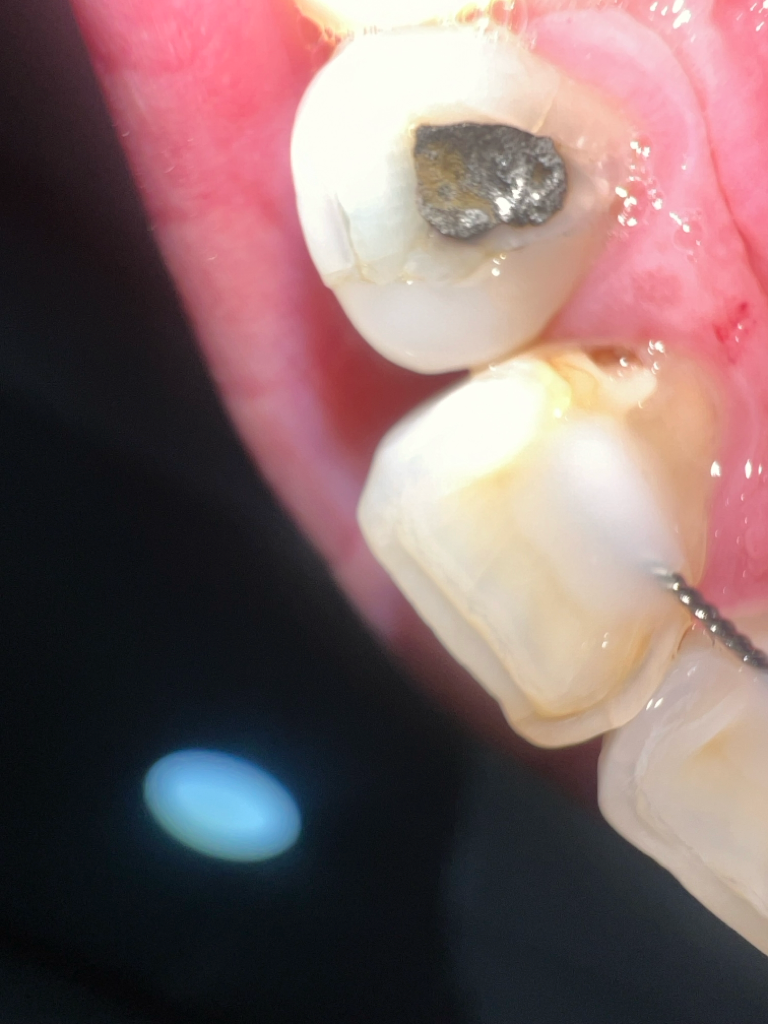

유지장치 쪽에 충치가 생겼다면 제거 후 먼저 충치치료를 받은 후에 다시 유지장치 끼면 됩니다

충치가 간단한거라면 저 상태에서 레진으로 치료를 하시면되지만, 신경치료를 하게된다면 유지장치를 제거하셔야될것같습니다.

충치치료가 우선이기에 우선 치과에 충치치료를 진행을 하고, 교정유지장치를 제거후 다시 새로 부착하길 권장드립니다.

충치의 크기가 작다면 유지장치를 굳이 제거하지 않고 해당 부위만 충치 치료 받으시면 될 수도 있지만, 그 크기가 커서 유지장치를 제거하지 않으면 기구 접근이 안 되는 경우에는 유지장치를 제거하고 충치 치료를 받으신 후 유지장치를 재제작하여 부착하시는 방법밖에는 없습니다.